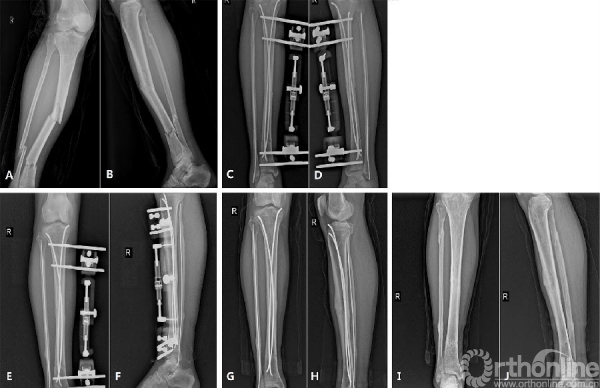

图4

图5